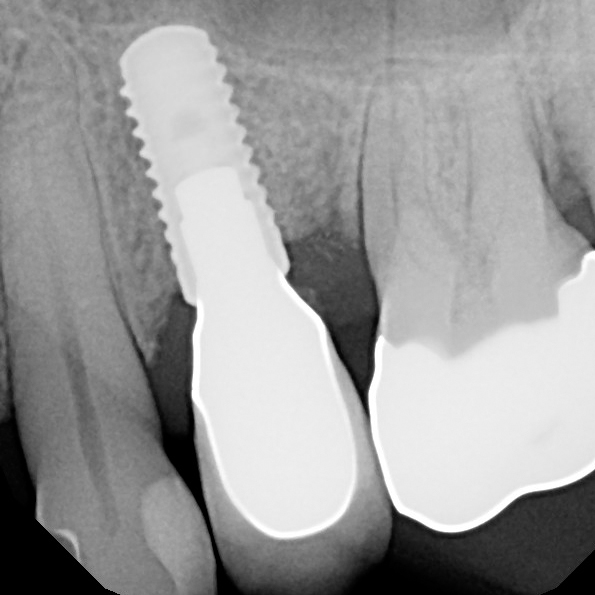

The implant system is a Straumann Bone Level RC implant.

The first slide shows an abutment that has been tapped for the set screw. And the following slides show the insertion of the set screw and the view from the lingual. The set screw system we are using is a product by Bredent.